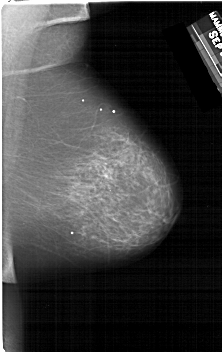

A_1260_1.RIGHT_MLO

RIGHT_MLO LINES 6676 PIXELS_PER_LINE 4201 BITS_PER_PIXEL 12 RESOLUTION 43.5 NON_OVERLAY